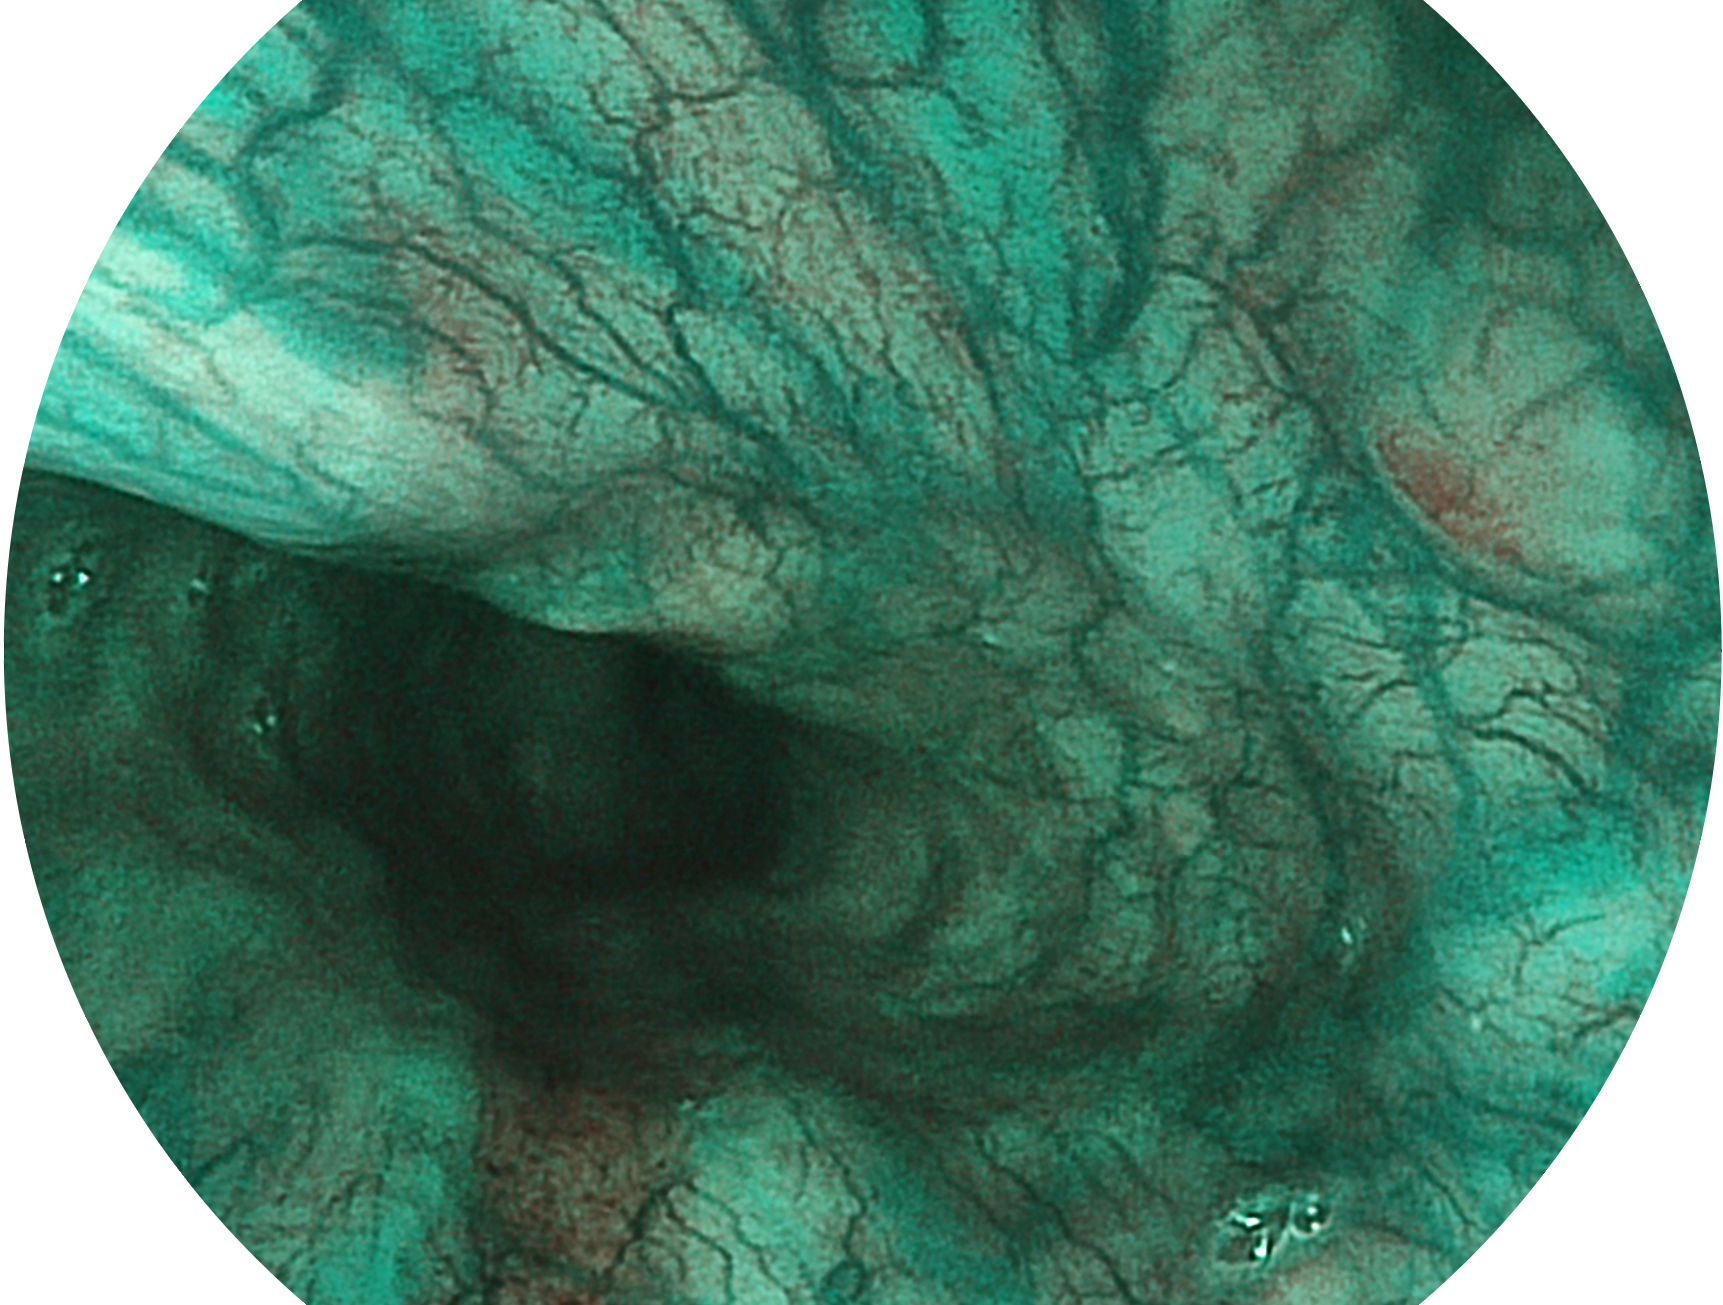

亚星官网新开发的内镜染色技术,主要是基于多波长LED 光源的开发,VLS-55Q 四波长LED 光源是由四个不同颜色的LED光按照相应照明模式所规定的特定发光比例进行合束后形成,合束后形成的照明光的光谱由红光、绿光、蓝光及蓝紫光这四个不同的波段范围构成。具有更高光谱自由度,通过光谱比例的控制,实现了聚谱成像技术,英文全称为“Spectral Focused Imaging, SFI”,缩写为“SFI”和光电复合染色成像技术,英文全称为“Versatile Intelligent Staining Technology, VIST”,缩写为“VIST”。